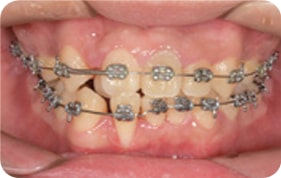

Case 2

2017. 08. 07

2018. 04. 16